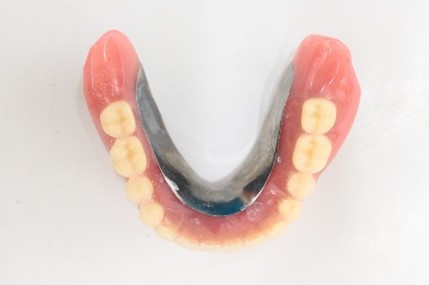

【マグネット式総入れ歯】

上顎

下顎

マグネット式総入れ歯

緑丸は組み込まれたマグネット

通常の総入れ歯

マグネット義歯

下顎マグネット義歯